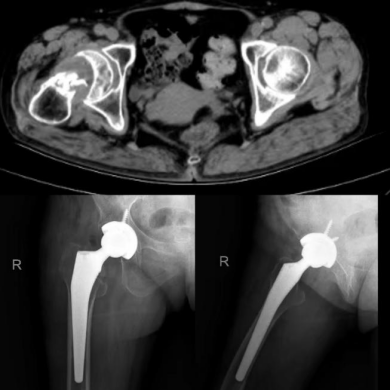

医生接诊后,通过专业查体、检查,明确了卢阿姨的腿痛并不是“皮外伤”,而是股骨颈骨折。腿痛的原因找到了,但由于长时间延误,患者股骨颈已经磨损殆尽,CT图像上只剩下股骨头和股骨粗隆。

骨伤中心李三忠主任介绍,一般股骨颈骨折会有患肢短缩、外旋畸形,但有一些特殊的像嵌插型骨折不会有这些畸形,而是表现为髋部疼痛,行走时加重,这个需要拍X线才能诊断出。像卢女士的情况,如果当时及时就诊,还可进行保髋治疗,而现在只能选择髋关节置换,不仅身体遭罪,花费也更高。

怀化市中医院骨伤中心髋、膝、肩、桡骨小头等人工关节置换手术日益成熟,目前,卢阿姨已进行髋关节置换手术,现在腿痛已经缓解,正在逐步康复。再此,医生也提醒广大市民群众,如遇身体不适,不要拖延,一定要及时就诊,以免小病变大病。(陈潜)